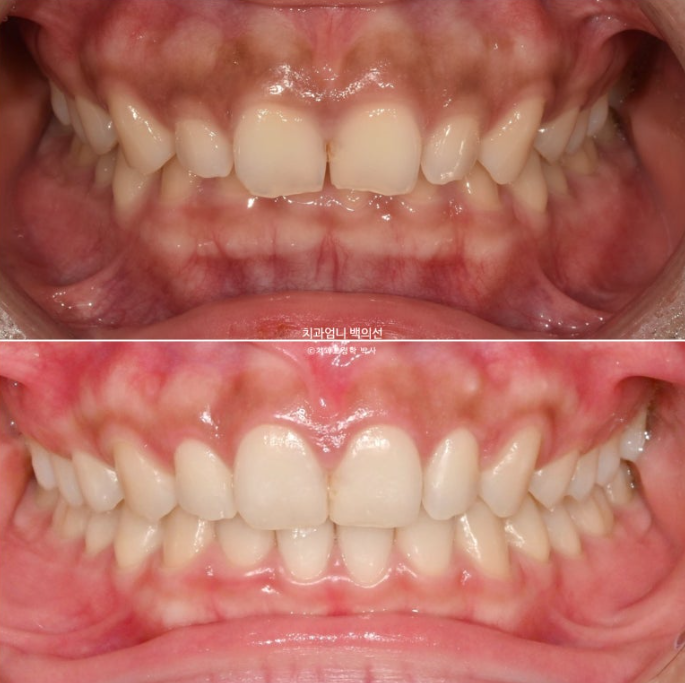

오늘은 앞니가 깊게 물리는 과개교합과 거미스마일이 있을 때 인비절라인 라이트로 단기간에 어떤 것을 할 수 있는 지 보여드리겠습니다.

24년 3월 잇몸성형을 위해 오신 분입니다.

위 앞니 4개가 전반적으로 짧은 편이고 웃을 때 잇몸이 많이 보이는 거미스마일이 있습니다.

잇몸성형으로 거미스마일을 어느정도는 해결할 수 있지만 앞니가 뒤로 쓰러진 옥니이고 깊게 물리는 과개교합도 있고 앞니 사이도 벌어져 있어서 교정을 권유드렸습니다.

위 앞니가 아래 앞니를 깊게 덮어 아래앞니가 전혀 보이지 않는 정도의 심한 과개교합입니다.

과개교합이 해소되며 아래앞니가 비로소 모습을 드러냅니다.

벌어진 틈을 깔끔하게 사라졌습니다.

삐뚤했던 앞니배열도 좋아졌습니다.

3.5개월의 변화라고 보기 힘들정도로 환자분은 열심히 껴주었고 치료계획도 완벽했습니다.

길이가 짧아 답답해보이던 앞니가 잇몸성형으로 비율이 좋아지며 보기에 시원해졌습니다.

이제 전후 비교 보겠습니다.

과개교합의 확실한 개선

거미스마일은 많이 개선이 되었습니다.

앞니가 뒤로 쓰러져 있던 옥니도 상당히 개선되었습니다.